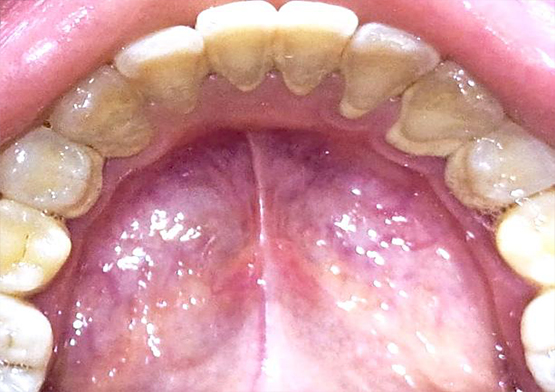

Gigi yang tidak terawat, selain bisa timbul penyakit juga menyebabkan mulut tidak sedap. Itu pasti akan sangat mengganggu keseharian kamu. Apalagi hingga munculnya karang gigi karena plak yang dibiarkan membuat tampilan gigi tampak tidak terawat. Pasalnya, plak yang mengeras cenderung berwarna kusam, bisa berwarna kuning kecokelatan hingga hitam.

Plak dan karang gigi mengandung jutaan bakteri dan jika tidak dibersihkan secara rutin, dapat menyebabkan periodontitis, kerusakan gigi, atau bahkan hilangnya gigi. Plak dan karang gigi sulit dihilangkan dengan penyikatan biasa, sehingga membutuhkan tindakan dan alat khusus melalui prosedur scaling. Selain untuk membersihkan plak dan karang gigi, scaling gigi juga bermanfaat untuk: